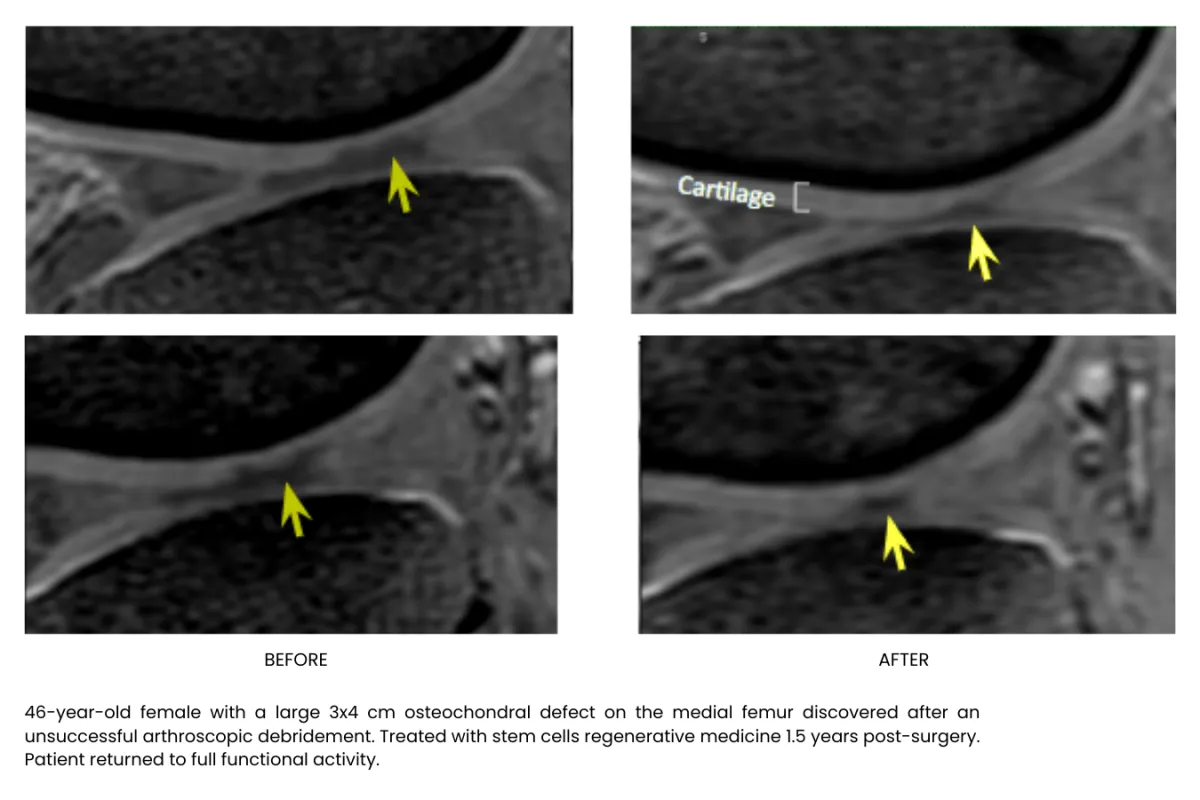

Millions of stem cells delivered precisely in the injured area building up tissue, recovering and freeing your from pain, without surgery or long recoveries.